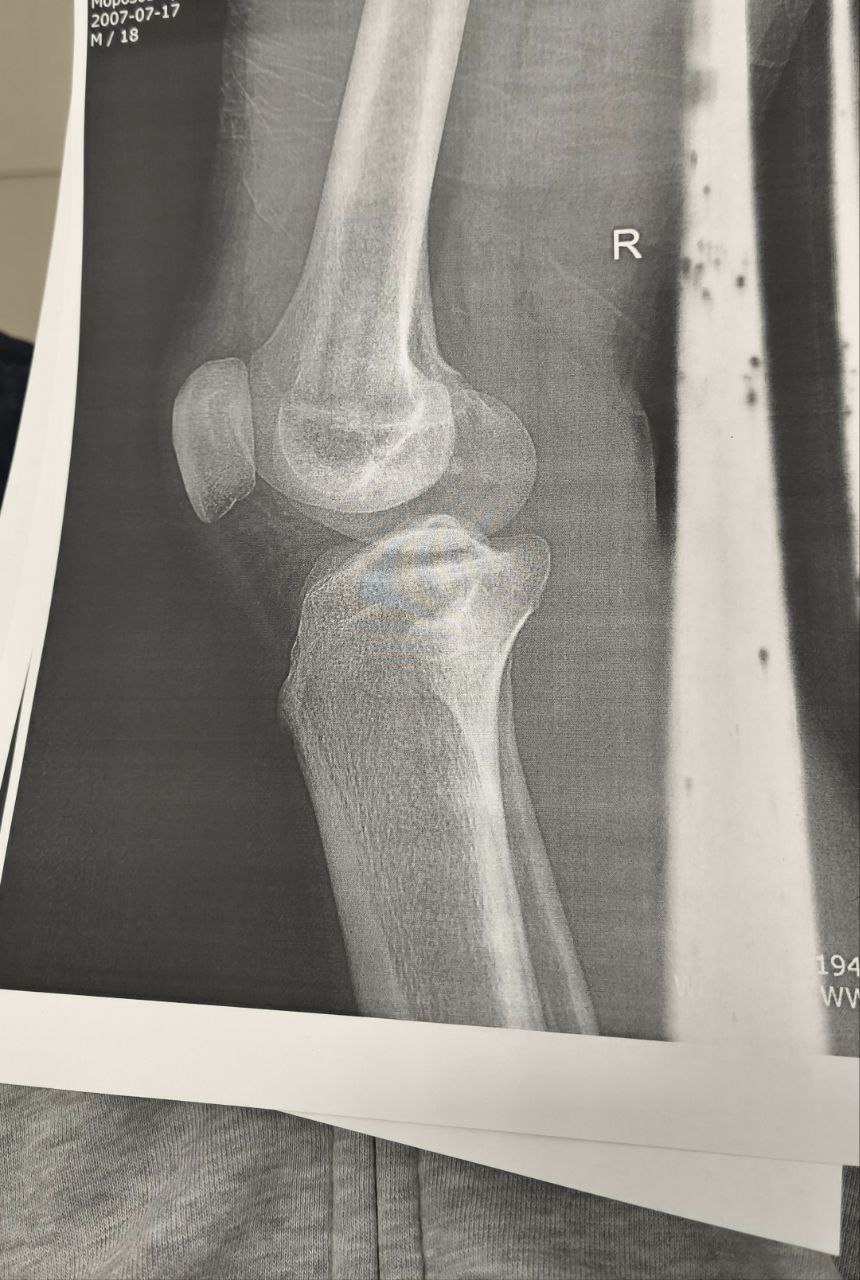

Помогите расшифровать снимок